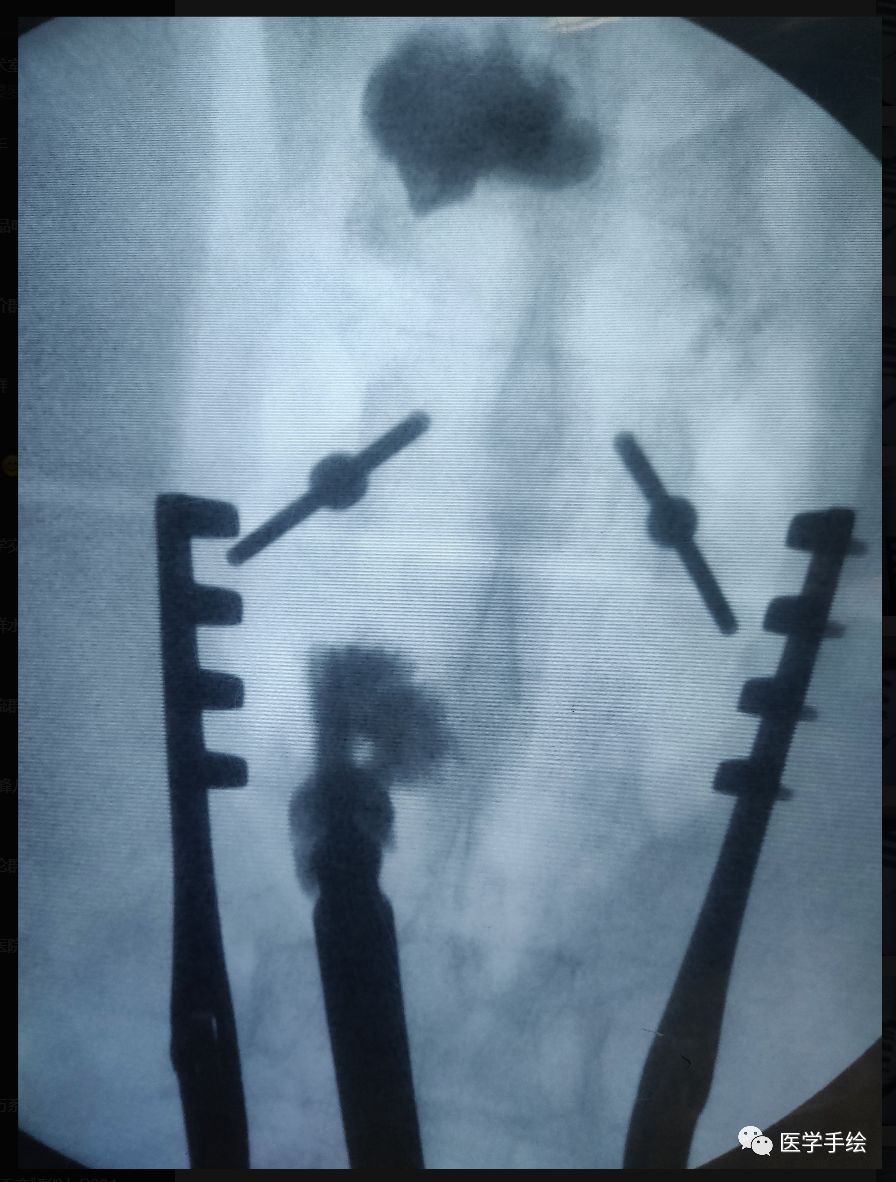

Santoni于2009年报道了皮质骨轨迹置钉技术(cortical bone trajectory,CBT)。

CBT螺钉进针点位于峡部,贴近脊柱的中线,靠内的进针点可以有效的避免对肌肉的剥离及关节突周围内侧神经支的干扰。尤其适用于肥胖及腰背肌发达的患者。同时CBT增加了与皮质骨的接触,从而增加了牢靠性,适用于骨质疏松的患者。

该技术的另一优势是它可以作为传统椎弓根螺钉的补救技术。比如置钉错误,钉道扩大等。由于其与传统的椎弓根螺钉的方向截然不同,可显著降低损伤椎管内神经的风险。

技术要点:1.进针点位于峡部外侧缘的内侧3mm部位。正位上是椎弓根“鹰眼”内缘垂线与下缘线的交点。

2.常规应用2mm磨钻进行钻孔,否则钻孔十分困难。制备骨道时应不断的应用磨钻头进行试探。国人的头倾角一般为20°-25°,外展角9°-10°。具体角度还应该根据术中的透视确定。一般选用直径4.5mm或5.0mm,长度25-30mm的特制螺钉。

case:老年骨质疏松患者,既往L2行单侧(左侧)椎体成形手术。本次手术L2需要置入螺钉,左侧椎弓根螺钉由于骨水泥的存在置入困难,选择CBT螺钉。